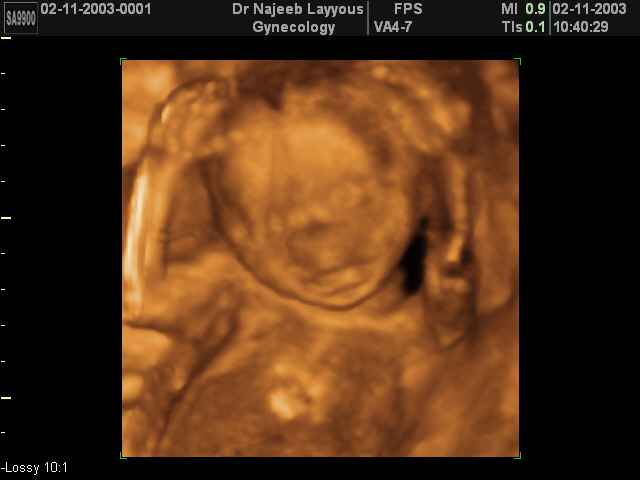

- Fetal Behavior Ultrasound Photos

Ultrasound Photos in 3D showing Fetal Behavior Inside the uterus | Dr N Layyous